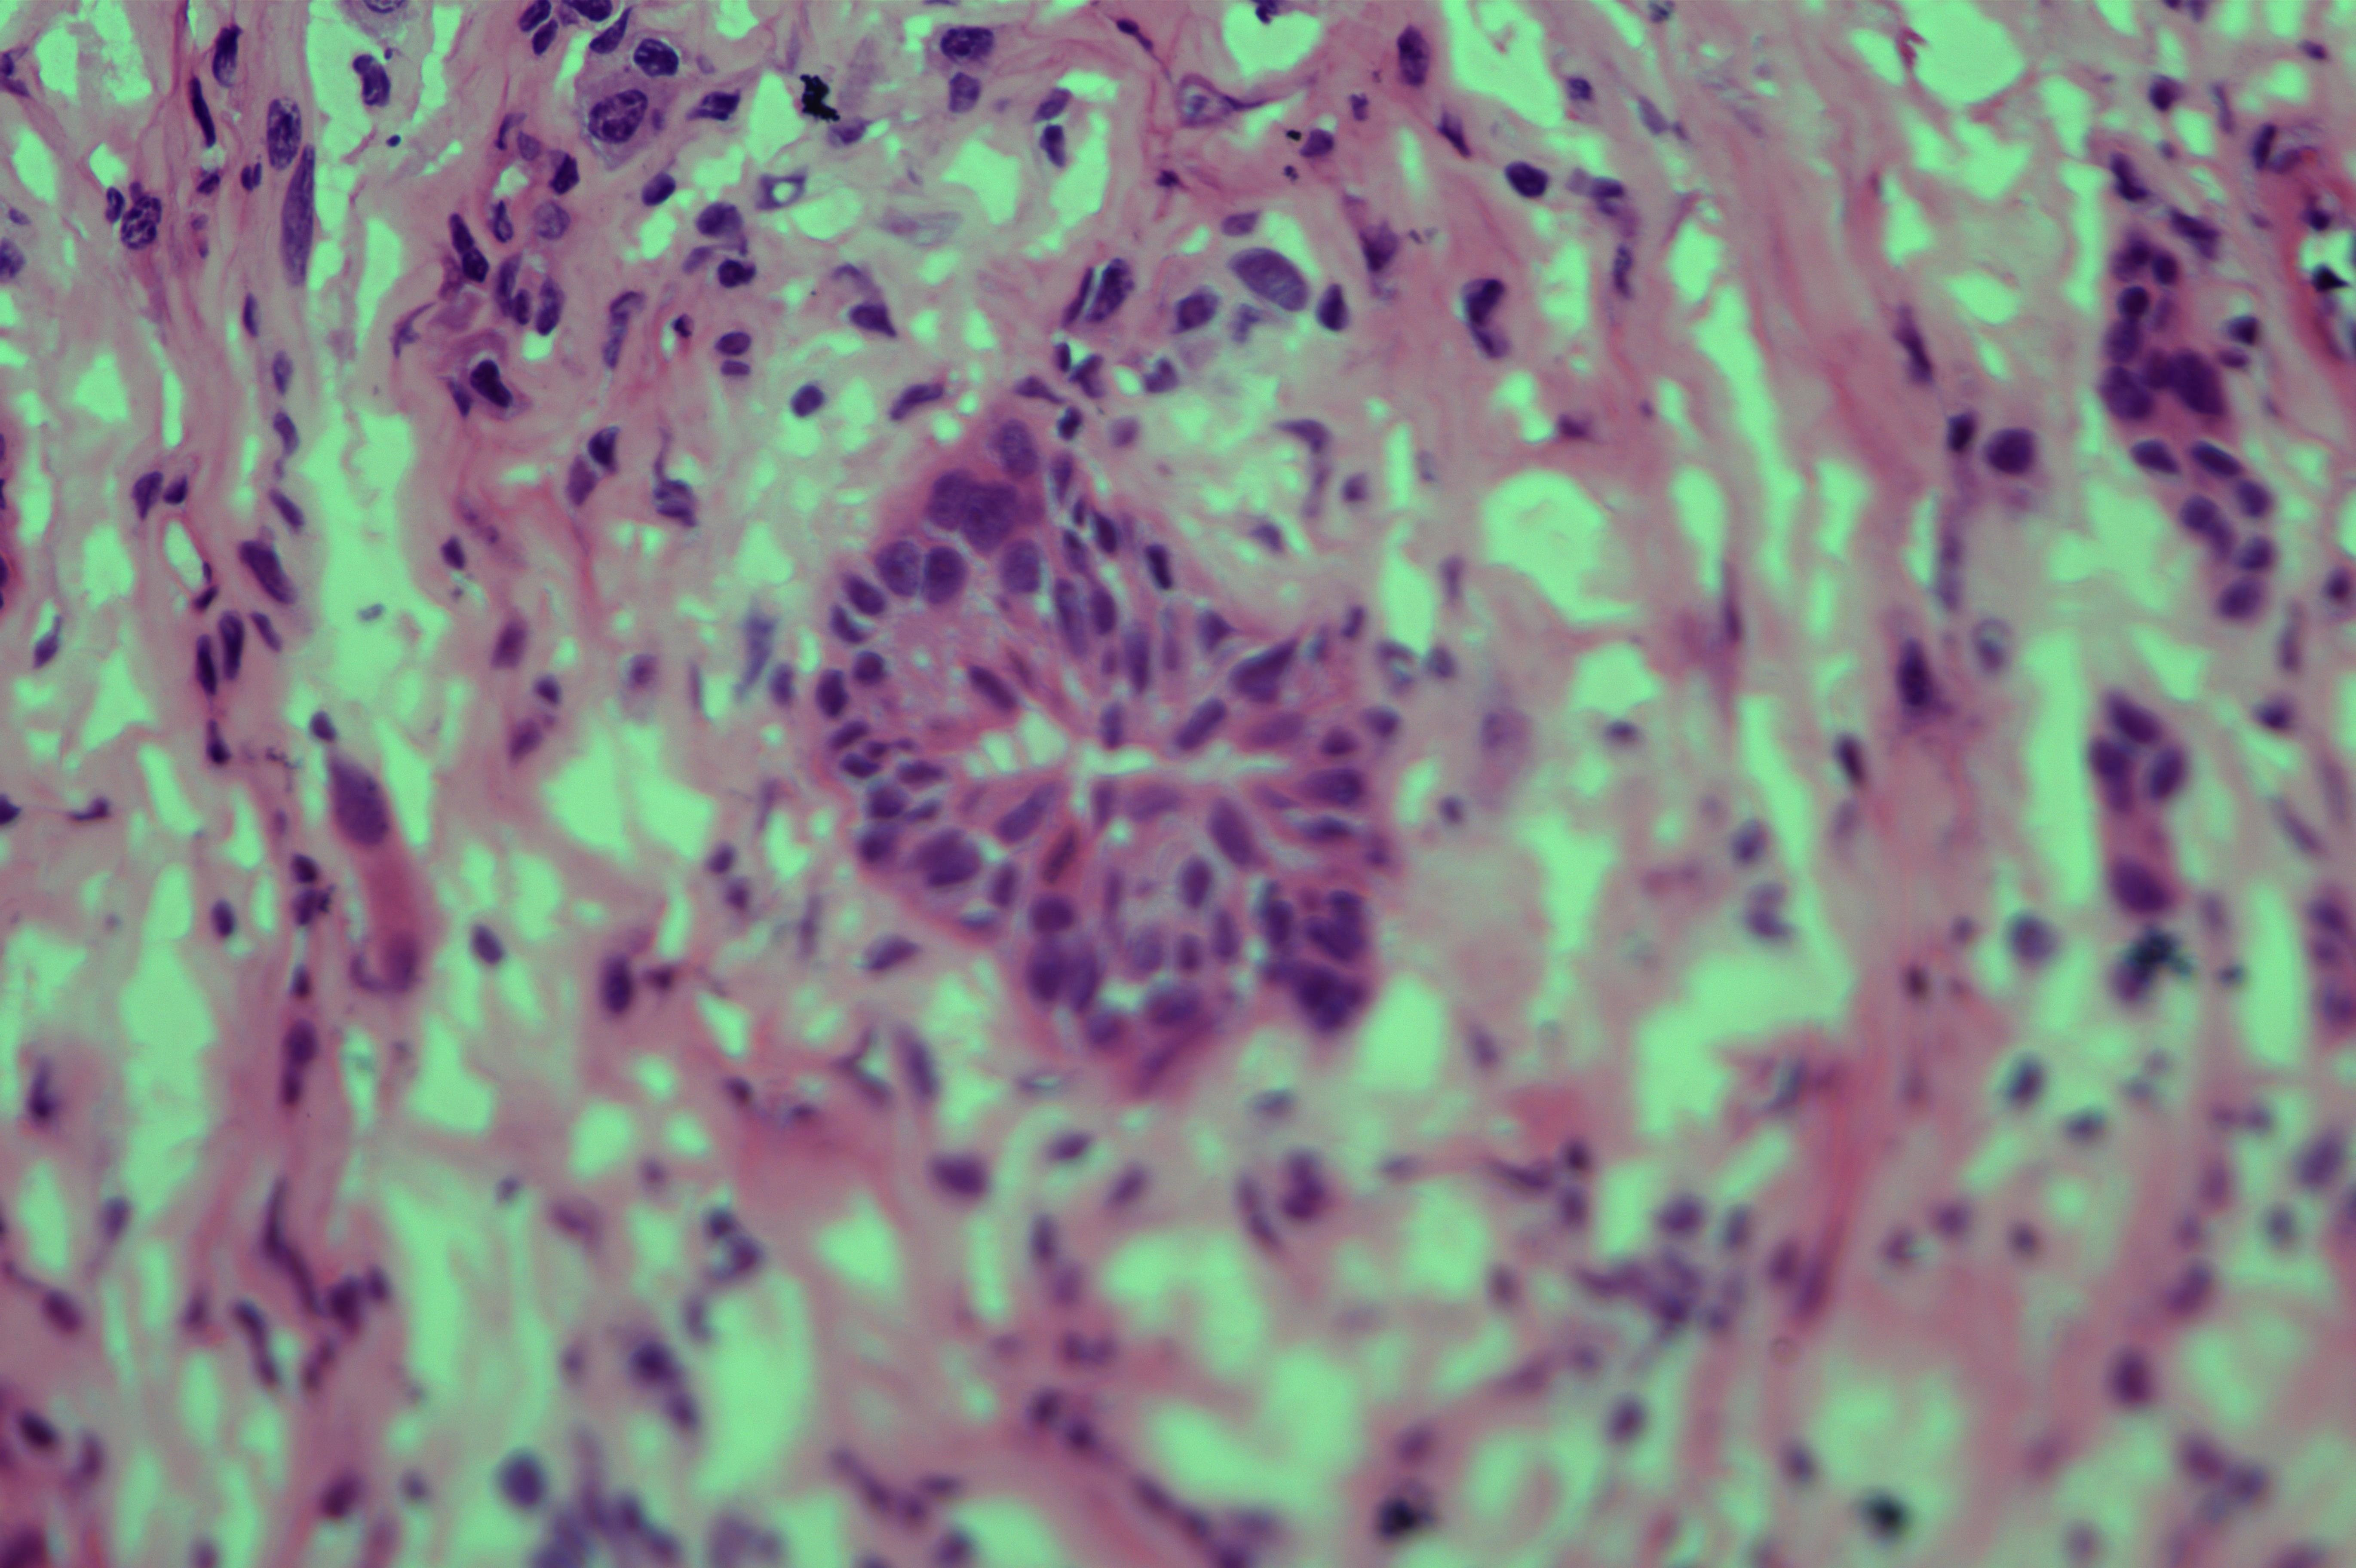

胰头肿物性质待诊

胰头肿物

上腹痛5天入院,核磁发现胰头囊肿,考虑良性

胰头囊肿

7x7x1.5cm囊肿一个,囊内见暗红色粘稠样物,囊壁厚0.7cm。

考虑为胰腺实性假乳头状瘤

会诊结果 :实性假乳头状瘤